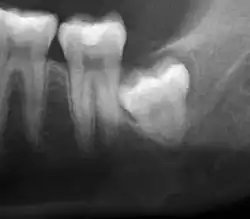

Impacted wisdom teeth are classified by their direction of impaction, their depth compared to the biting surface of adjacent teeth and the amount of the tooth's crown that extends through gum tissue or bone. Impacted wisdom teeth can also be classified by the presence or absence of symptoms and disease. Screening for the presence of wisdom teeth often begins in late adolescence when a partially developed tooth may become impacted. Screening commonly includes a clinical examination as well as x-rays such as panoramic radiographs.

Diagnosis

The diagnosis of impaction can be made clinically if enough of the wisdom tooth is visible to determine its angulation, depth, and if the patient is old enough that further eruption or uprighting is unlikely. Wisdom teeth continue to move to the age of 25 years old due to eruption, and then continue some later movement owing to periodontal disease.[18]

If the tooth cannot be assessed with clinical exam alone, the diagnosis is made using either a panoramic radiograph or cone-beam CT. Where unerupted wisdom teeth still have eruption potential several predictors are used to determine the chance of the teeth becoming impacted. The ratio of space between the tooth crown length and the amount of space available, the angle of the teeth compared to the other teeth are the two most commonly used predictors, with the space ratio being the most accurate. Despite the capacity for movement into early adulthood, the likelihood that the tooth will become impacted can be predicted when the ratio of space available to the length of the crown of the tooth is under 1.[5]: 141